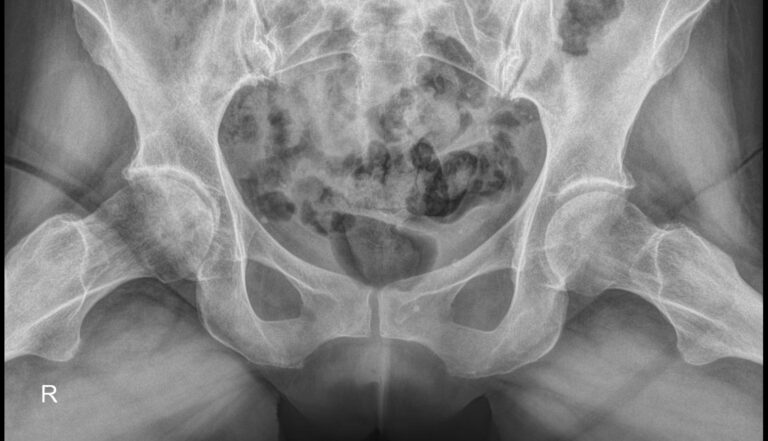

Рентгеновское исследование ― классический метод диагностики костно-суставных патологий. Он основан на способности ионизирующего излучения проходить сквозь ткани и поглощаться ими в большей или меньшей степени. Кости, как наиболее плотные в организме, поглощают большее количество излучения и на классическом негативном снимке выглядят светлыми образованиями. Видны и все изменения в костях и окружающих их структурах.

Рентгеновское исследование в 2 проекциях ― прямой и по Лаунштейну ― входит в список обязательных диагностических процедур при многих болезнях, поражающих тазобедренный сустав. Снимки необходимы как для подбора терапевтического лечения, так и для планирования оперативного вмешательства при эндопротезировании.

Что показывает рентген тазобедренных суставов в прямой проекции и по Лаунштейну

• Контуры костей суставов, линии переломов;

• Соответствие сочленяющихся поверхностей;

• Суставную щель и ее особенности;

• Состояние костной ткани, очаги разрежения;

• Новообразования;

• В положении Лаунштейна особенно четко видна головка бедренной кости и ее изменения.